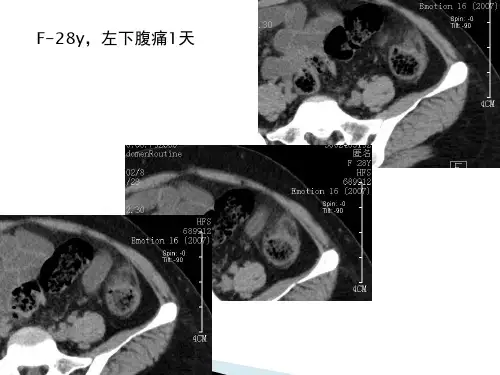

急性肠脂垂炎PPT课件